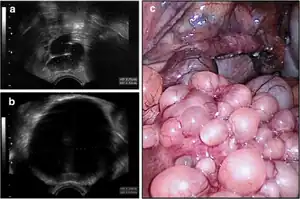

| Tubo-ovarian abscess | ![]() | |

| Endosalpingiosis | ![]() |